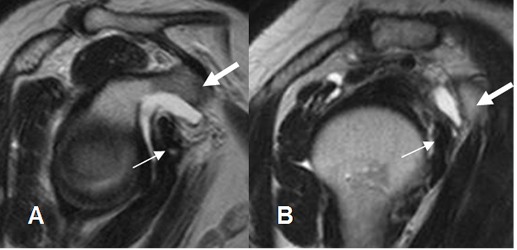

Fig 144. Bursitis subdeltoidea crónica.

A: Rx AP. Calcificación gruesa por encima de la tuberosidad mayor, por tendinitis o bursitis crónica.

B: RM coronal en T1 y C: RM coronal en STIR. Ausencia de señal por calcificación gruesa (Flecha delgada), por encima del tendón del supraespinoso el cual conserva su señal. (Flecha gruesa). Los cambios son compatibles con bursitis crónica.